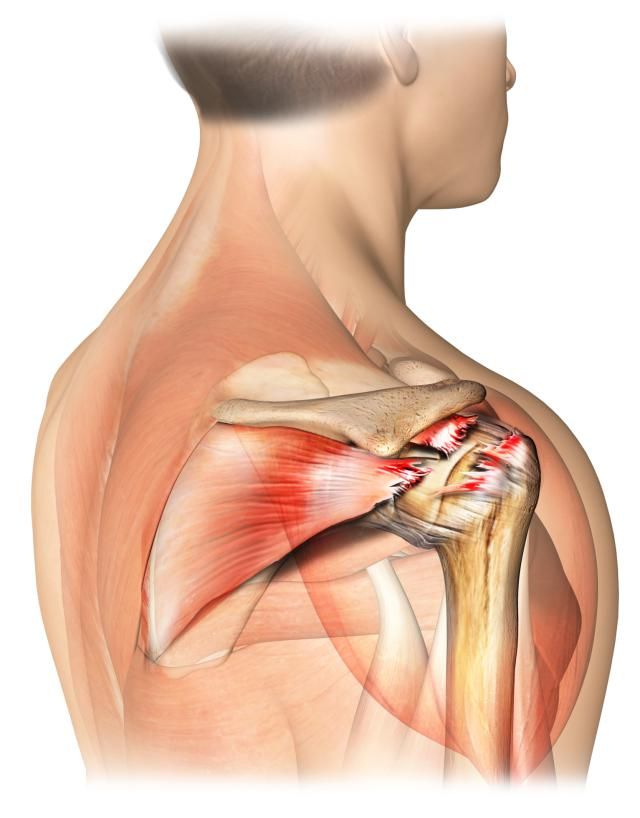

●肩袖损伤:肩袖是一个非常复杂的结构,我们通常也称之为旋转袖,分别由冈上肌,冈下肌,肩胛下肌以及小圆肌的肌腱构成。肩袖对于肩关节的整个活动起到了非常重要的作用,同时还有稳定肩关节的作用。

导致肩袖损伤的原因有很多,比如外伤、比如退化、比如肩关节撞击。

肩袖出现损伤的患者,疼痛比较明显,在夜间的时候可能会出现明显的加重,而且患者有可能出现典型的“疼痛弧”,也就是活动到一定角度的时候疼痛开始出现,但随着角度的加大,疼痛慢慢的减轻了,有一些患者随着病情时间的延长,会出现肩关节的肿胀,出现肩关节的粘连!

但如果是肩袖全层撕裂,患者疼痛比较明显,肩关节的功能严重受限,而且患者有主观意愿,想要解决问题的时候,需要进行肩关节镜手术治疗,对肩袖进行缝合或者是止点重建。